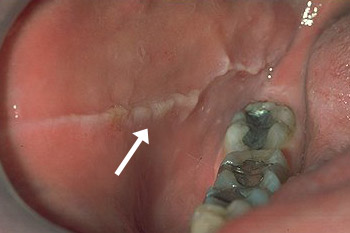

Linea alba

Linea alba betekent letterlijk witte lijn. Deze witte lijn kan op het wangslijmvlies voorkomen, meestal dubbelzijdig en ter hoogte van de lijn waar de kiezen elkaar ontmoeten bij het dicht bijten. De afwijking veroorzaakt eigenlijk nooit klachten en je kan het verklaren met vorming van littekenweefsel door het trauma van herhaaldelijk dicht bijten op de wang.